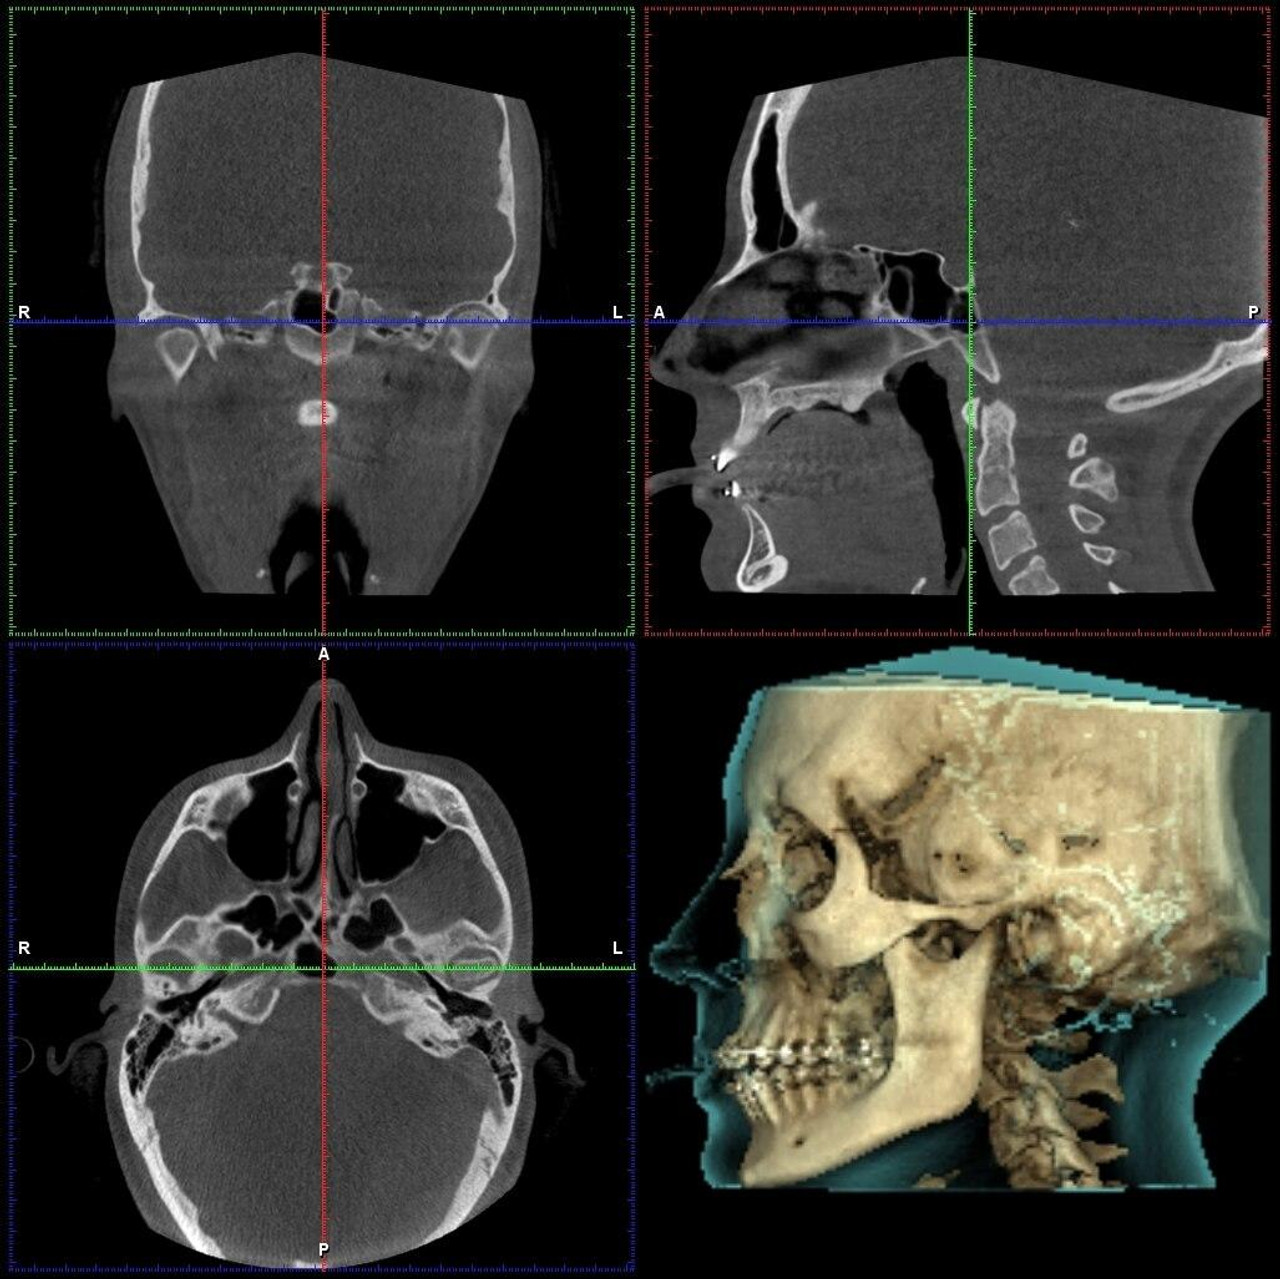

- Knowledge of the normal anatomical features seen on images taken of the teeth, oral cavity, jaws, facial structures and of the head and neck region.

- Practical training sessions and hands-on case interpretations of volumes on CBCT software.

- Anatomic review in various anatomic planes

- Interpretation of the images of disorders that affect the oral & maxillofacial region.

- Introduction to the software followed by Hands-On.

- CBCT in Endodontics – Imaging protocols & interpretation of aberrant canal anatomy, localisation of accessory canals, calcified canals, root fractures, broken instruments, pulp stones etc.

- Sleep disorders, airway analysis and TMJ analysis